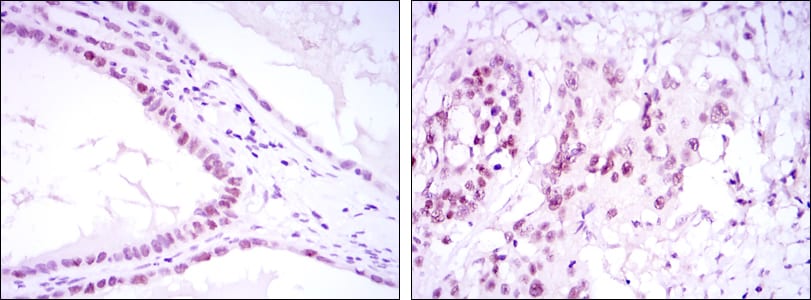

IHC 1/200 - 1/1000 Human,Mouse,Rat

SUZ12 antibodies are widely used to investigate PRC2's function in chromatin remodeling, stem cell differentiation, and disease pathogenesis, particularly cancer. They enable detection of SUZ12 protein expression levels, localization, and PRC2 complex assembly via techniques like Western blot, immunohistochemistry (IHC), immunofluorescence (IF), and chromatin immunoprecipitation (ChIP). Validated antibodies typically target conserved regions of SUZ12. such as its N-terminal or C-terminal domains.